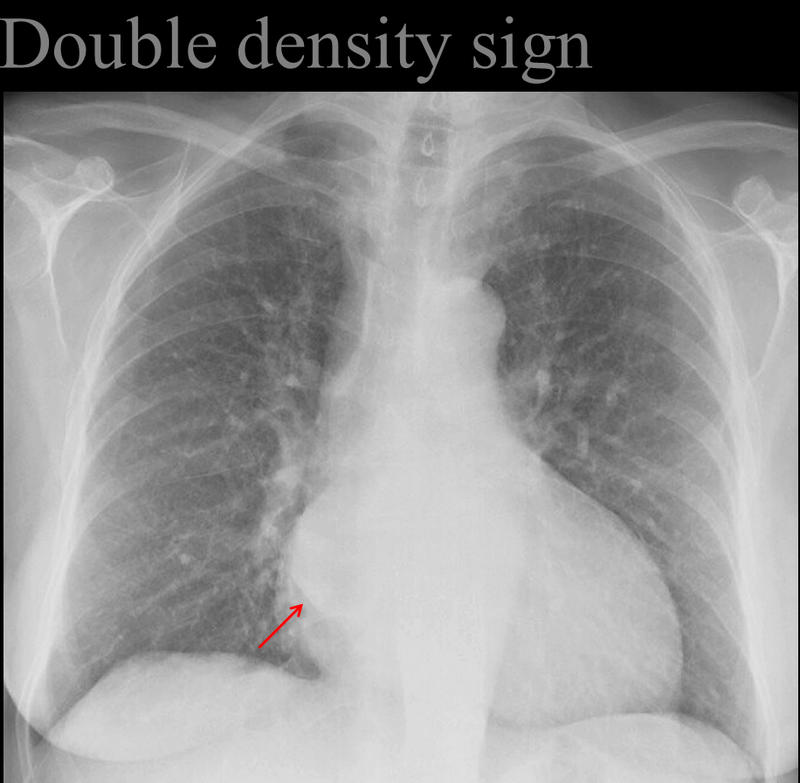

Double density sign

Left atrial enlargement